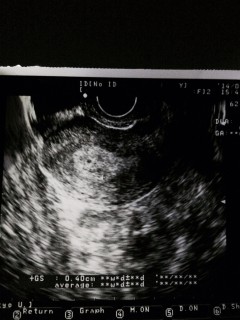

たぶんこれが胎嚢って言われました!笑たぶんって…笑

次は四日後です(^○^)